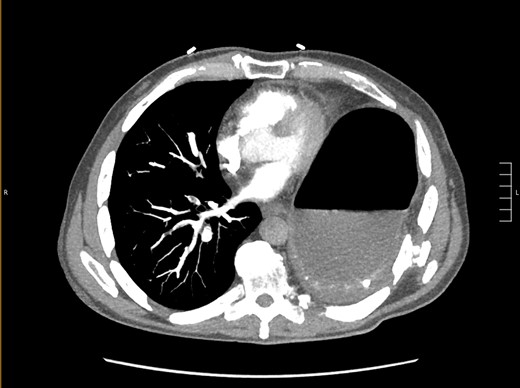

Thirty-seven days after the initial visit, the patient returned to the emergency department with burning epigastric pain that radiated to the left upper chest and hematemesis. Vital signs revealed tachycardia and hypertension. A comprehensive physical exam was significant for decreased breath sounds at the left base and tenderness in the left upper quadrant without signs of peritonitis. Pertinent laboratory findings showed leukocytosis with a left shift and thrombocytosis. A chest X-ray showed a significant portion of the gastric body in the left hemithorax (Fig. 1). A pulmonary CT angiogram found segmental and subsegmental pulmonary emboli in both lungs with no evidence of right heart strain and a left pleural effusion. A left diaphragmatic hernia with the “dangling diaphragm” sign can be seen on the sagittal view (Fig. 2). The coronal view shows discontinuity of the diaphragm and the “collar” sign (Fig. 3); the axial view shows the “dependent viscera” sign and thoracic fluid abutting abdominal viscera (Fig. 4).

Axial CT showing previously fractured ribs, the “dependent viscera” sign, and thoracic fluid abutting abdominal viscera.